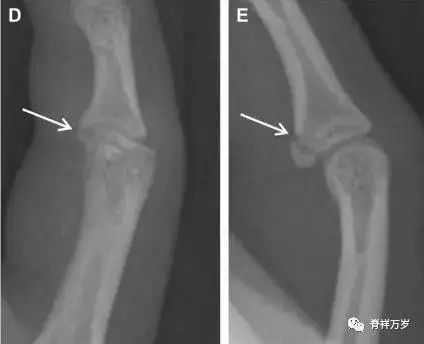

Essex-Lopresti 损伤

Essex-Lopresti 损伤是桡骨头骨折伴有下尺桡关节脱位,导致骨间膜损伤,桡骨短缩。此种损伤,桡骨头骨折的诊断往往是明确的,容易忽视的是下尺桡关节脱位,特别是早期,下尺桡关节的症状不明显,X 线表示也不明显。

图 8 Essex-Lopresti 损伤。前后位(A)和侧位(B)示桡骨头关节内骨折(白色实线箭头);(C~E)伤后 1 个月复诊,患者诉腕关节疼痛,X 线(C,D)发现下尺桡关节脱位,(E)CT 进一步证实损伤的存在。